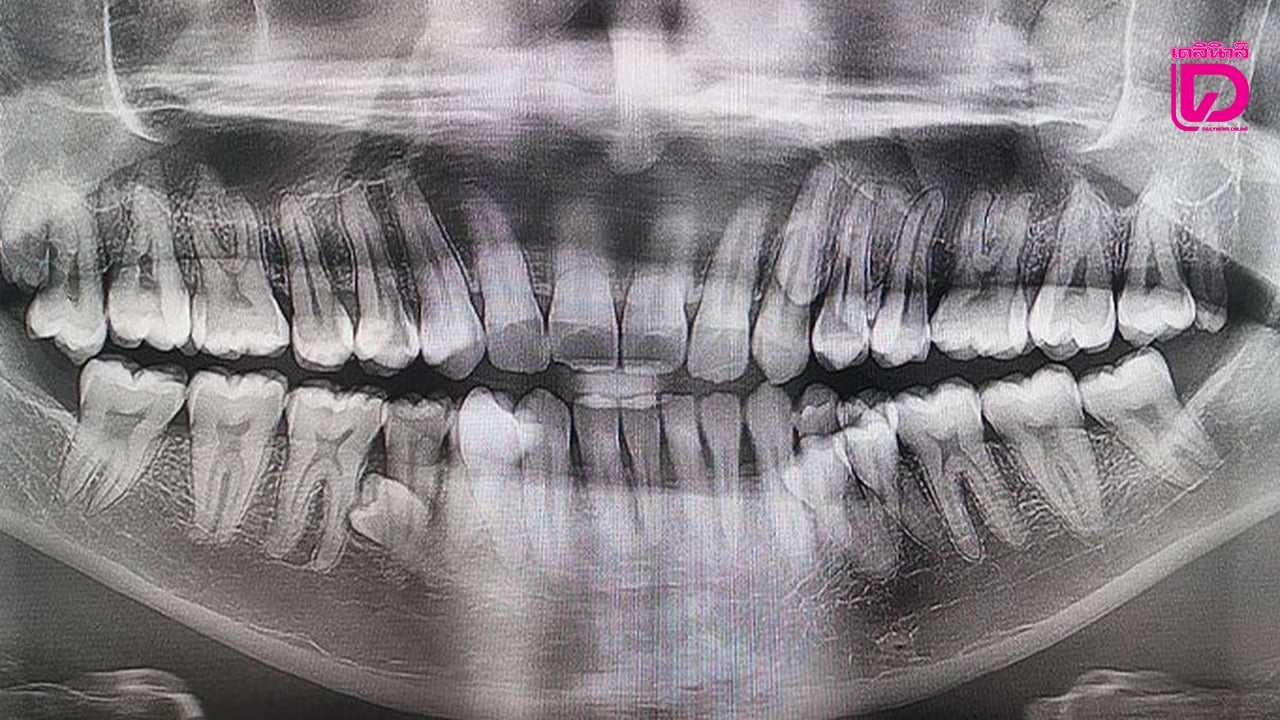

ถ้าคุณคิดว่าการดูแลฟัน 32 ซี่เป็นเรื่องยาก ลองนึกถึงชายคนนี้ดู ล่าสุด กินเนสส์เวิลด์เรคคอร์ด (Guinness World Records) เพิ่งให้การรับรองสถิติโลกใหม่ กับชายชาวมาเลเซียวัย 33 ปี ปราตาป มุนยันดี (Pratap Muniyandi) หลังจากผลตรวจทางทันตกรรมยืนยันว่าเขามีฟันรวมกันถึง 42 ซี่ คนปกติมีฟัน 32 ซี่ แต่ ปราตาป มี 42 ซี่ (เกินมา 10 ซี่!)

เขาเริ่มเอะใจเมื่อ 5 ปีก่อนตอนนั่งดื่มชา แล้วรู้สึกว่ามีฟันงอกเพิ่มขึ้นเรื่อยๆ จากที่นับได้ 38 ซี่ จนพุ่งไปถึง 42 ซี่ในช่วงต้นปี 2023 ที่น่าทึ่งที่สุดคือ ฟันส่วนเกินเหล่านี้ “ขึ้นมาอย่างเป็นระเบียบ” และไม่รบกวนชีวิตประจำวันของเขาเลย

ก่อนหน้านี้ ในปี 2024 เด็กหญิงชาวบราซิล ทำสถิติมีฟันทั้งหมด 81 ซี่ รวมทั้ง ฟันน้ำนม ฟันแท้ และฟันเกิน แต่ ปราตาป เป็นผู้ครองสถิติฟันแท้มากสุด